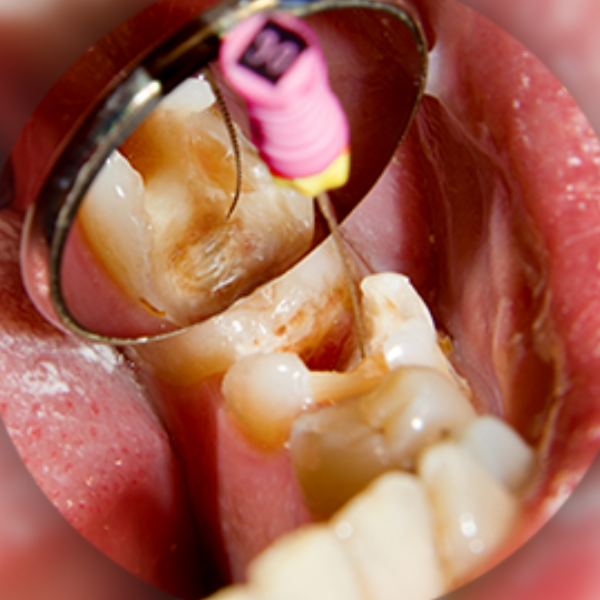

What Is Root Canal Treatment?

Precision Endodontic Therapy for Infected Teeth

Root canal treatment is a dental procedure that removes infected or damaged pulp inside a tooth. After cleaning and disinfecting the root canal, the tooth is sealed and restored with a filling or crown to prevent further infection.

Unlike extraction, this treatment preserves your natural tooth, maintaining bite alignment and jaw stability.

At our advanced RCT Clinic in Hyderabad, we use rotary instruments and magnification tools to improve precision and patient comfort.